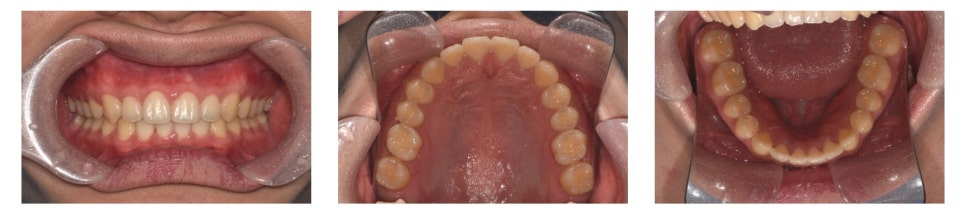

치료 시작 약 1년 후 모습입니다.

하악 중절치 사이의 공간(spacing)이 거의 닫혔고, deep bite 역시 많이 개선된 모습을 볼 수 있습니다.